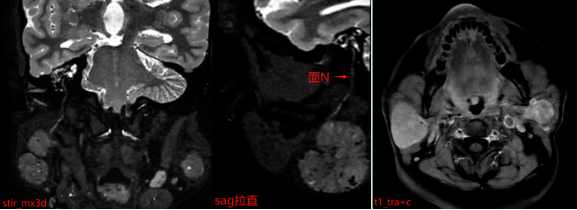

MR表现:双侧腮腺浅叶下极见结节状略混杂信号,T1以低信号为主、T2以 稍高信号为主,DWI呈稍高信号,ADC图呈稍低信号,边界清晰,增强扫描病变中等强化,强化较均匀,其内见点状无强化影。

为什么影像检查中要“加扫”特殊序列?

报告中特别提到“加扫stir_mx3d序列”,这一步骤非常重要。该序列能更清晰地显示病变与周围神经、血管的解剖关系。腮腺区域内走行着重要的面神经,它控制着我们的面部表情肌肉。如果手术中损伤该神经,可能导致术后面瘫,影响患者闭眼、微笑等基本功能。